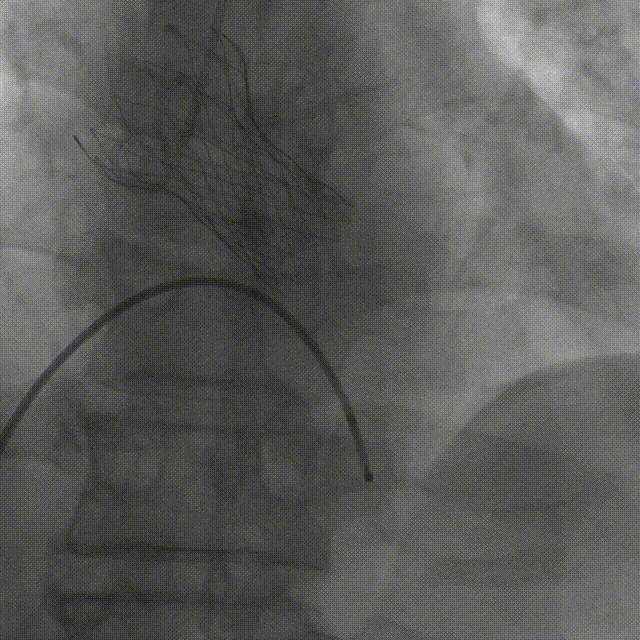

TaurusNXT植入过程

术中影像

主动脉根部造影

TaurusAtlas 18mm球囊预扩张

瓣膜释放至工作位造影

最终造影